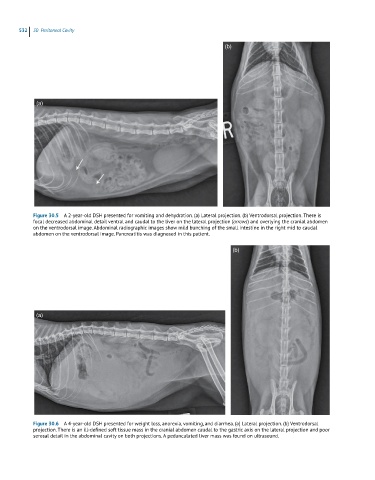

Figure 30.5 A 2-year-old DSH presented for vomiting and dehydration. (a) Lateral projection. (b) Ventrodorsal projection. There is

focal decreased abdominal detail ventral and caudal to the liver on the lateral projection (arrows) and overlying the cranial abdomen

on the ventrodorsal image. Abdominal radiographic images show mild bunching of the small intestine in the right mid to caudal

abdomen on the ventrodorsal image. Pancreatitis was diagnosed in this patient.

Figure 30.6 A 4-year-old DSH presented for weight loss, anorexia, vomiting, and diarrhea. (a) Lateral projection. (b) Ventrodorsal

projection. There is an ill-defined soft tissue mass in the cranial abdomen caudal to the gastric axis on the lateral projection and poor

serosal detail in the abdominal cavity on both projections. A pedunculated liver mass was found on ultrasound.